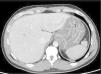

A 36-year-old male patient with no medical history of immunosuppression arrived at the emergency department with intense epigastric pain and fever. Due to persistent elevation of acute phase reactants, an urgent abdominal computed tomography (CT) scan was performed, visualizing increased mural thickness and submucosal edema of the gastric wall, suggestive of a gastric inflammatory process (Fig. 1). He presented with rapid deterioration and was transferred to the intensive care unit (ICU). Subsequently, an upper endoscopy was carried out, describing enlarged gastric folds (Fig. 2). The histologic study of the gastric biopsies showed acute inflammation and necrosis at the mucosa and submucosa (Fig. 3), with positive cultures for Streptococcus pyogenes. Despite antibiotic treatment, his response was poor, and he consequently underwent urgent surgery with total gastrectomy. The patient’s recovery was adequate, and he was discharged without incidents.